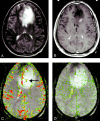

Background and purpose: Relative cerebral blood volume (rCBV) and vascular permeability (K(trans)) permit in vivo assessment of glioma microvasculature. We assessed the associations between rCBV and K(trans) derived from dynamic, susceptibility-weighted, contrast-enhanced (DSC) MR imaging and tumor grade and between rCBV and K(trans).

Methods: Seventy-three patients with primary gliomas underwent conventional and DSC MR imaging. rCBVs were obtained from regions of maximal abnormality for each lesion on rCBV color maps. K(trans) was derived from a pharmacokinetic modeling algorithm. Histopathologic grade was compared with rCBV and K(trans) (Tukey honestly significant difference). Spearman and Pearson correlation factors were determined between rCBV, K(trans), and tumor grade. The diagnostic utility of rCBV and K(trans) in discriminating grade II or III tumors from grade I tumors was assessed by logistic regression.

Results: rCBV was significantly different for all three grades (P </=.0005). K(trans) was significantly different between grade I and grade II or III (P =.027) but not between other grades or combinations of grades. Spearman rank and Pearson correlations, respectively, were as follows: rCBV and grade, r = 0.817 and r = 0.771; K(trans) and grade, r = 0.234 and r = 0.277; and rCBV and K(trans), r = 0.266 and r = 0.163. Only rCBV was significantly predictive of high-grade gliomas (P <.0001).

Conclusion: rCBV with strongly correlated with tumor grade; the correlation between K(trans) and tumor grade was weaker. rCBV and K(trans) were positively but weakly correlated, suggesting that these parameters demonstrate different tumor characteristics. rCBV is a more significant predictor of high-grade glioma than K(trans).